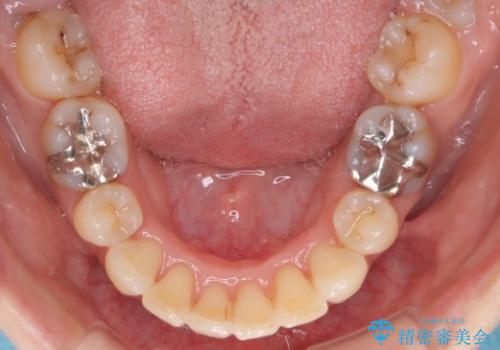

上顎の前歯は前方に傾斜して、下顎の前歯は強いガタガタが見られました。

前から4番目の歯を上下左右合計2本抜歯して、歯並びを整える計画としました。